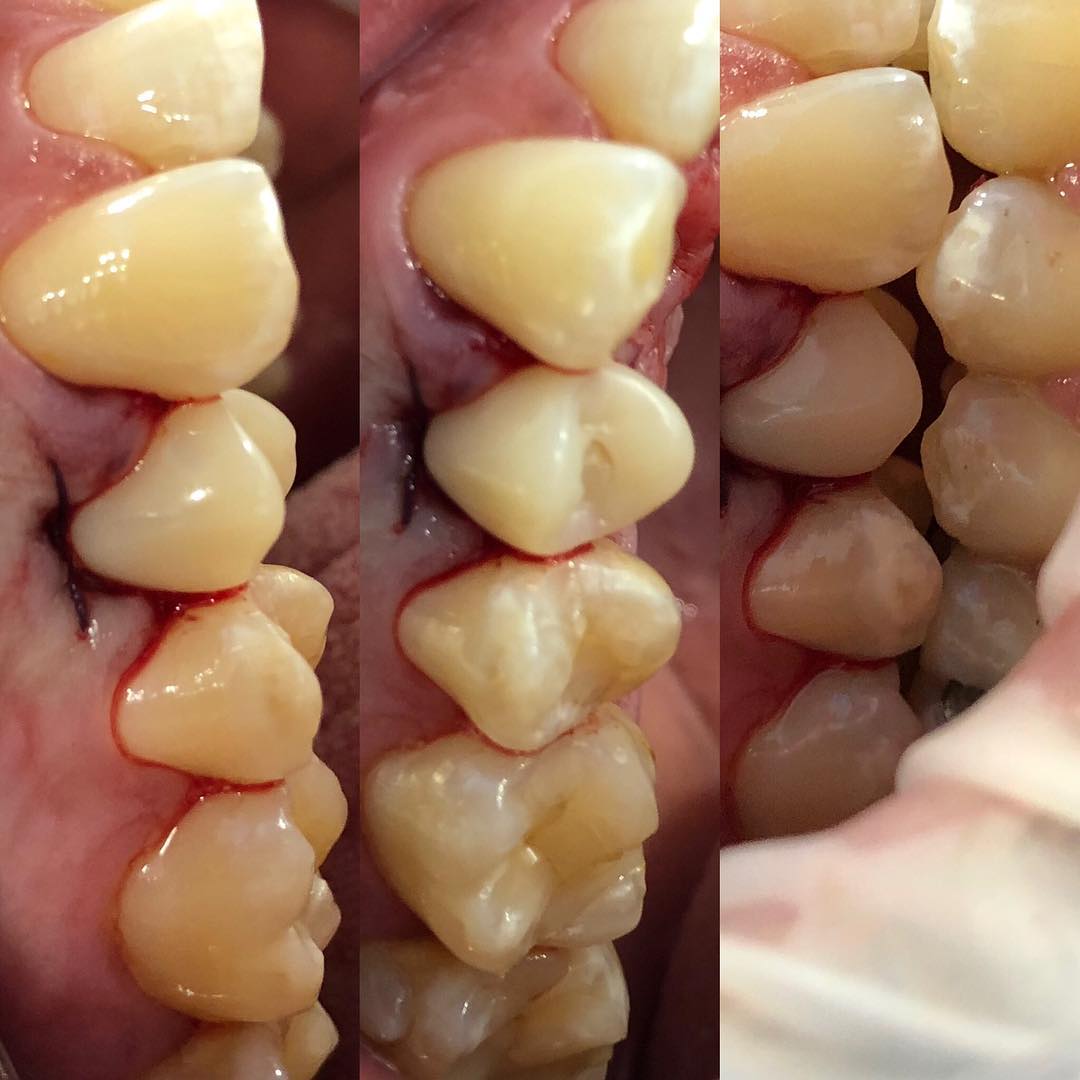

...Se presenta un caso clínico de restauración directa en resina composite, ejemplo del valor de la precisión y la técnica meticulosa incluso en procedimientos considerados rutinarios dentro de la práctica diaria. El caso pone en evidencia la importancia del control de la morfología, la textura y la integración cromática, así como del adecuado aislamiento del campo operatorio y la estratificación del material, factores determinantes para conseguir un resultado natural, funcional y duradero. A través de una ejecución cuidadosa, se logró una restauración estéticamente imperceptible y funcionalmente estable, que respeta los principios de mínima invasión y adhesión efectiva. Este tipo de procedimientos, aunque cotidianos, reflejan la constancia y el nivel de exigencia clínica necesarios para ofrecer odontología de calidad en todos los casos, independientemente de su complejidad.